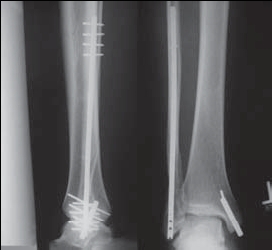

Если и оперировать, то, наверное, целесообразно бы поставить IP-XSL (long nail). И косметический дефект минимальный, и нагрузка сразу и удалять нет особой необходимости.

2. при повреждении г/стопного сустава тактика описана в руководствах, и учитывая повышенные функциональные требования возможно и операция, как

вариант БИОС м/берцовой кости и позиционный винт на синдесмоз, оценить состояние дельтовидной связки.

Невозможно устранить проблему фиксацией малоберцовой пластиной или другими методами, потому что главная проблема - разрыв межберцовой мембраны, которая находится между костями и внизу в голеностопе в синдесмозе.

Две параллельных шурупа создают условия для сращения мембраны и синдесмоза, 8 недельный срок достаточен, и можно удалить фиксаторы.

Без оперативного лечения Межкостная мембрана будет источником боли у спортсменов.